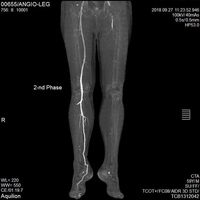

Инструментальные исследования • Дуплексное ультразвуковое ангиосканирование с использованием цветного допплеровского картирования — метод выбора в диагностике тромбоза ниже уровня паховой связки. Основной признак тромбоза: обнаружение эхопозитивных тромботических масс в просвете сосуда. Эхоплотность возрастает по мере увеличения «возраста» тромба •• Перестают дифференцироваться створки клапанов •• Диаметр пораженной вены увеличивается в 2–2,5 раза по сравнению с контралатеральным сосудом, вена перестаёт реагировать на компрессию датчиком (признак, особенно важный в первые дни заболевания, когда тромб визуально не отличим от нормального просвета вены) •• Неокклюзионный пристеночный тромбоз хорошо выявляется при цветном картировании — пространство между тромбом и стенкой вены прокрашивается синим цветом •• Флотирующая проксимальная часть тромба имеет овальную форму и располагается центрально в просвете сосуда • Рентгеноконтрастная ретроградная илиокаваграфия применяется в тех случаях, когда тромбоз распространяется выше проекции паховой связки, поскольку УЗИ тазовых сосудов затрудняется из-за кишечного газа.

Цветовая дуплексная сонография и ультразвуковое допплеровское исследование — дают максимум информации о состоянии венозных путей и прилегающих тканей, места расположения тромба, объёма распространения.